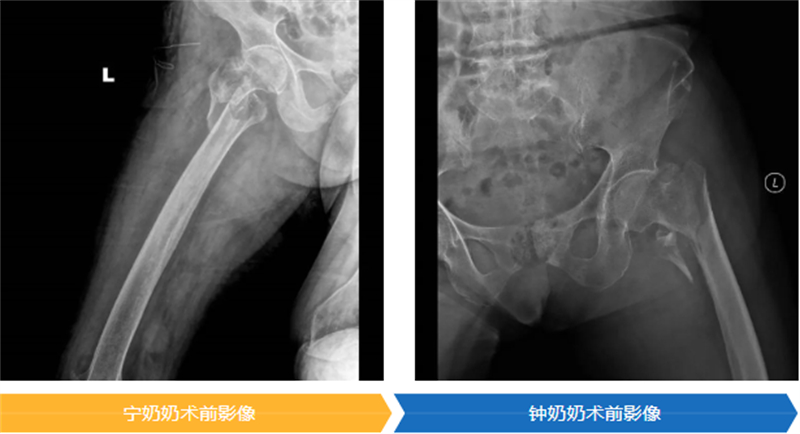

手術是讓老人重獲生機的關鍵一步,但同時也是對百歲高齡軀體的嚴峻挑戰。為了以最小的創傷換取最大的生存機會,醫療團隊為兩位老人精心選擇了“股骨近端防旋髓內釘(PFNA)”這一微創固定方案。

舒文主任醫師對此做了一個生動的比喻:“這個手術就像是處理一個內部斷裂的承重墻。不需要‘大拆大建’,只需通過一個很小的切口,在骨頭內部植入一個堅固的‘內置支架’,為骨折部位提供穩定支撐,如同架起一根‘鋼筋’,讓老人能夠盡早活動,從而避免臥床帶來的各種致命風險?!?/p>

時間就是生命。在醫院為高齡患者開通的綠色通道保障下,兩位老人均在入院24小時內接受了這關鍵性手術,并順利完成。隨后,在重癥監護室(ICU)團隊的晝夜精心守護下,兩位百歲老人平穩渡過了術后最危險的階段,為后續的康復贏得了寶貴的時機。

在大家溫暖的鼓勵和專業的幫助下,寧奶奶在手術后第三天,就穩穩地站起來了;鐘奶奶也在第五天,堅強地扶著助行器邁開了步子。能早點下床,就意味著能把肺炎、血栓這些“臥床病”遠遠推開,恢復得更順利,也能早一點回家。